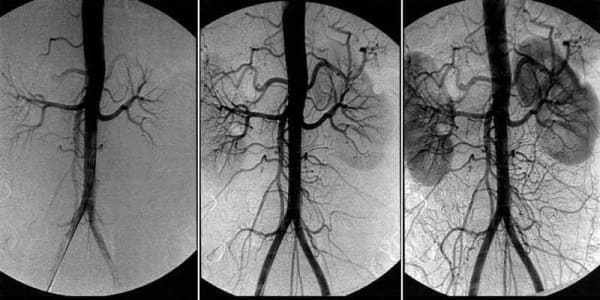

Agar boshingiz va oyoq-qo'llaringiz og'rib qolsa, quloqlaringizda shovqinlar sezilib qolsa nima qilish kerak? Miya tomirlarining angioedema belgilari.